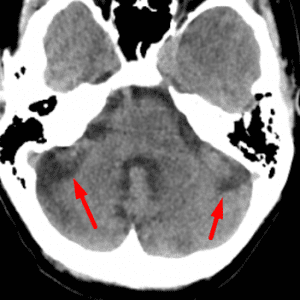

Choroid Plexus in Foramina of Luschka

Mimicking hemorrhage or a CP angle mass